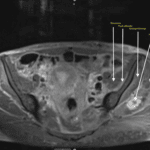

It is all about localization !

Patient was found down with left lower extremity weakness